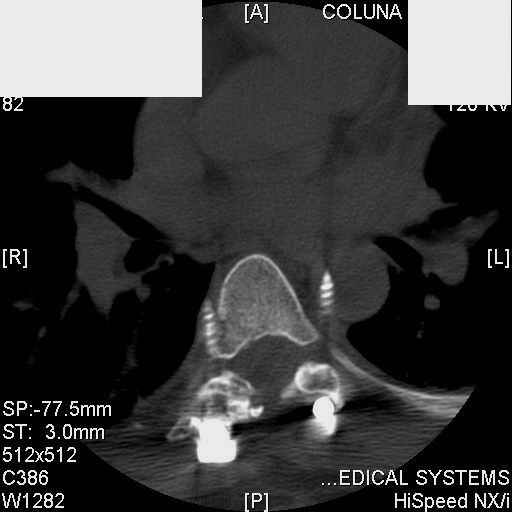

Interesting case. Findings on CT: all four pedicle screws have been placed improperly inthat they miss the vertebral bodies. In addition, the screws on the left side are impingingon the decending thoracic aorta. What I do NOT know is the nature of the original injury, orwhether or not that injury has resolved. I would recommend removal of the hardware. I don'tthink it's a good idea to leave those screws where they are. If the original fracture ishealed, nothing else needs to be done.

dear Mark, all the details are not yet available but the patient is coming to see us foradvice. We probably will see him in the early new year. i thought that the 4th picture showedthe screw to enter the aorta? He is a victim of a motor vehicle crash and thoracic vertebralfracture which appears healed. He was posteriorly decompressed and this device inserted. asyou say there isno evidenece that any of the fixation enters the bodies via the pediclesistead they have passed thru and their end are no where near where they ought to be. If I amcorrect (I would prefer not to be) the aortic intima has been breached by the screw. When thetime comes to take the screw out I thought we should have control of the aorta.What do you think?

Mark Thank you. He is scheduled for a angio prior to transfer here. I keep going back to lookat that fourth image and although it is tough to believe the wall of the aorta seems toencompass the distal 1/2 of the screw. I have come to anticipate mal postion of screws thathave been inserted in hospitals that perhaps may not have the highest quality of equipment,including the human and radiological components. That having been said this case seems tosurpass the usual... one screw out of place or screwed into a disc etc. BTW I am notsuggesting that the screw was placed directly into the aorta but that moviment, pulse actionetc may have caused it to transgress the normal anatomical bounds without evident hemorrhage.